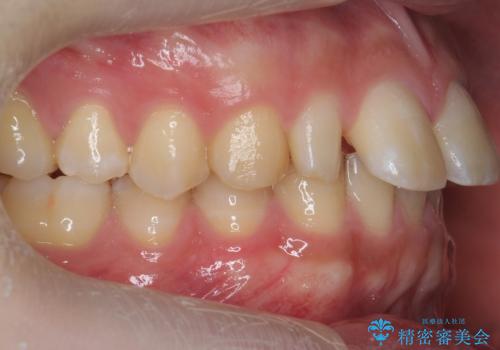

矯正治療で1番目の歯を寄せて2番目の歯はセラミックで形をととのえています。

上下のかみこみがきつい場合で上にだけすき間がある場合は、上のすき間を閉じきるのは難しいことが多いです。

理由としては、すき間を閉じるには上の前歯は後ろに下がる形に動かないと無理なのですが、かみこみがきつい(かみ合わせがきつい、上下が深く咬んでいるともいいます)場合は、すぐ後ろに下の歯がかみこむためその動きができないためです。

さらに下の前歯にがたつきがある場合は下の前歯を後ろに下げること自体が難しくなるため、生まれつき歯の形が特殊な場合は、上のすき間を適切な位置にずらして、しかるべき歯にセラミッククラウンを被せて形態修正とスペースを埋めるというのが効率の良い治療方法と言えます。